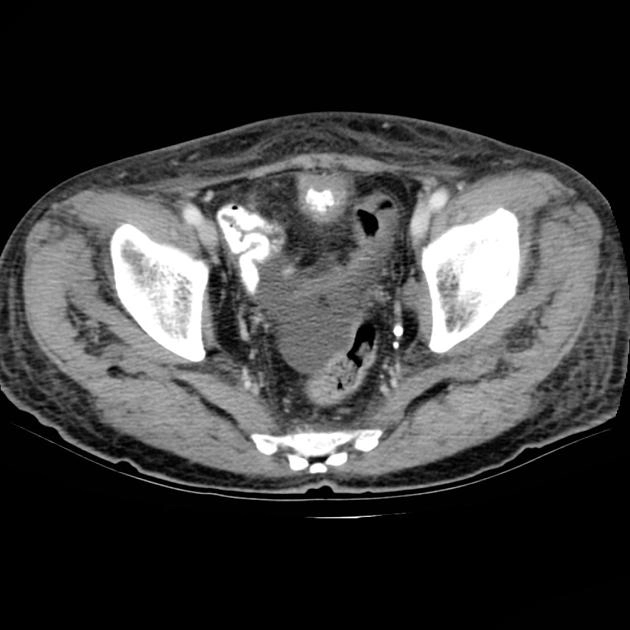

• Khối u bàng quang

U cơ trơn bàng quang (Leiomyoma of the urinary bladder)

Ung thư biểu mô tế bào chuyển tiếp ở bàng quang (Transitional cell carcinoma (urinary bladder))

Phân loại giai đoạn ung thư của bàng quang (Transitional cell carcinoma of the bladder (staging))

Ung thư biểu mô tuyến của bàng quang (Adenocarcinoma urinary bladder)